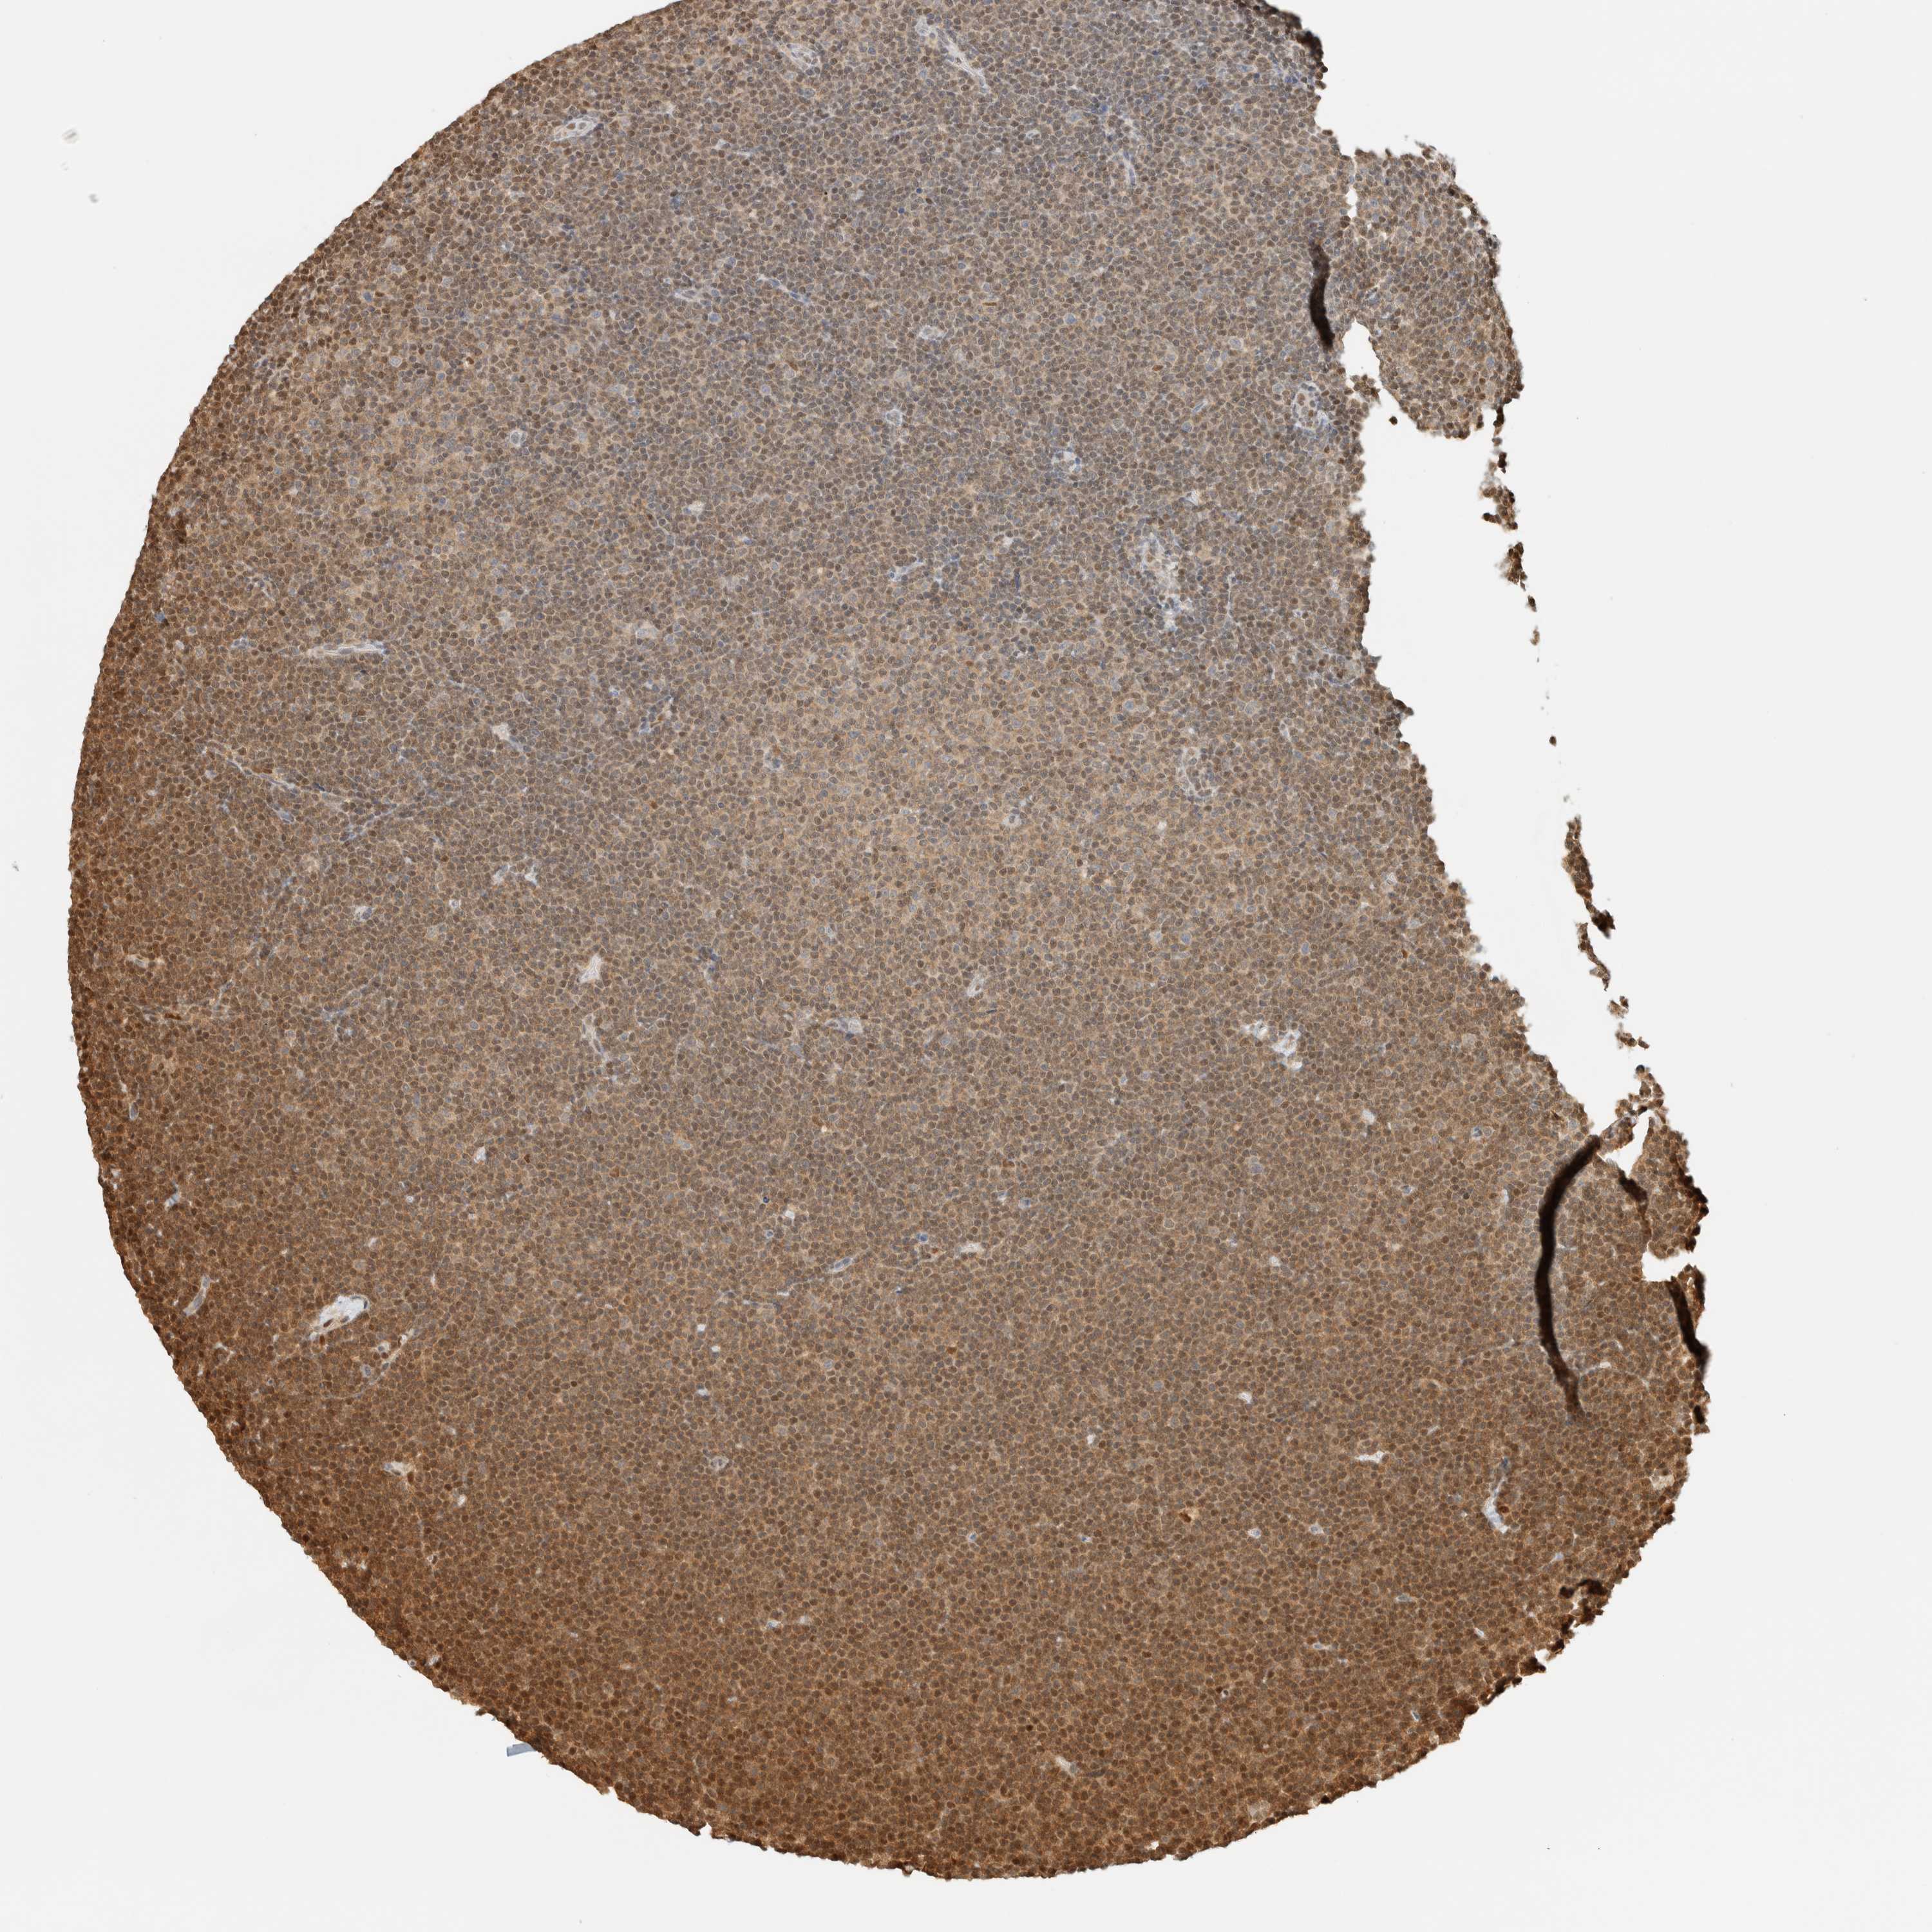

CANCER LYMPHOMA Show tissue menu

LYMPHOMA - Protein expressioni

A mouse-over function shows sample information and annotation data. Click on an image to view it in a full screen mode. Samples can be filtered based on level of antibody staining by selecting one or several of the following categories: high, medium, low and not detected. The assay and annotation is described here.

Each image is clickable and will lead to virtual microscopy that enables deeper exploration of all samples and also displays staining intensity scores, fraction scores and subcellular localization as well as patient and tissue information for each sample.

Antibody HPA023438

Staining

High

Intensity

Strong

Quantity

>75%

Location

Nuclear

Hodgkin's disease, NOS

Malignant lymphoma, non-Hodgkin's type, High grade

Malignant lymphoma, non-Hodgkin's type, Low grade